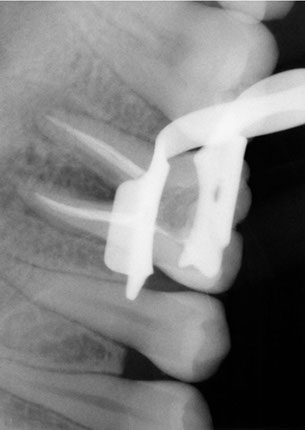

La endodoncia le da más tiempo de vida útil a su pieza dental, en Dental Evolution Cancún le recomendamos evitar la extracción realizándose este procedimiento que garantizamos será sin dolor, gracias a la tecnología de vanguardia con la que contamos, instrumental rotatorio, sistema de ultrasonido, y a nuestra “radiografía digital” la cual juega un papel crucial en el procedimiento de endodoncia, además de que usted estará atendido con la calidez, calidad humana y  profesionalismo que caracteriza a nuestro experto equipo de dentistas  especializados que le apoyaran en todo momento.